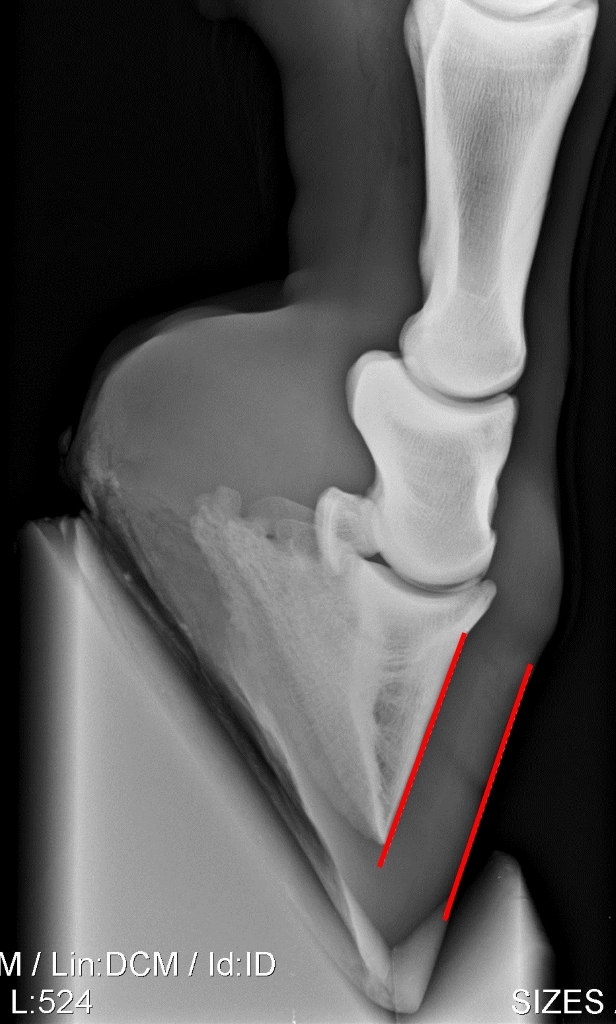

Als gevolg van de ontstoken lederhuid kan de verbinding tussen het hoefbeen en de hoefwand (deels) loslaten. Daardoor kan het hoefbeen gaan kantelen en er meer ruimte ontstaan tussen hoefbeen en hoefwand. Dit is het beste zichtbaar op röntgenfoto’s. De kanteling van het hoefbeen resulteert ook in een verbrede witte lijn. Op de lange termijn kan een kanteling van het hoefbeen zichtbaar blijven door een knikje in de hoefwand. Dat ontstaat doordat na een kanteling de hoefwand vanuit de kroonrand weer vlakker langs het hoefbeen af groeit terwijl de ontstane ruimte tussen hoefbeen en hoefwand verderop aanwezig blijft. In zeer ernstige gevallen kan de verbinding tussen hoefbeen en hoefwand zodanig verslechteren dat het hoefbeen niet alleen kantelt maar zelfs in zijn geheel gaat zakken binnen de hoefcapsule. Dit is een zeer ernstige complicatie waarbij het zover kan gaan dat het hoefbeen door de zool heen drukt, een zoolbreuk.

Zijdelingse röntgenopnames van ondervoeten, de hoefwand en het hoefbeen zijn met rode lijnen geaccentueerd. Links een normale ondervoet zonder gekanteld hoefbeen. Rechts een röntgenopname van een vrij ver gekanteld hoefbeen.